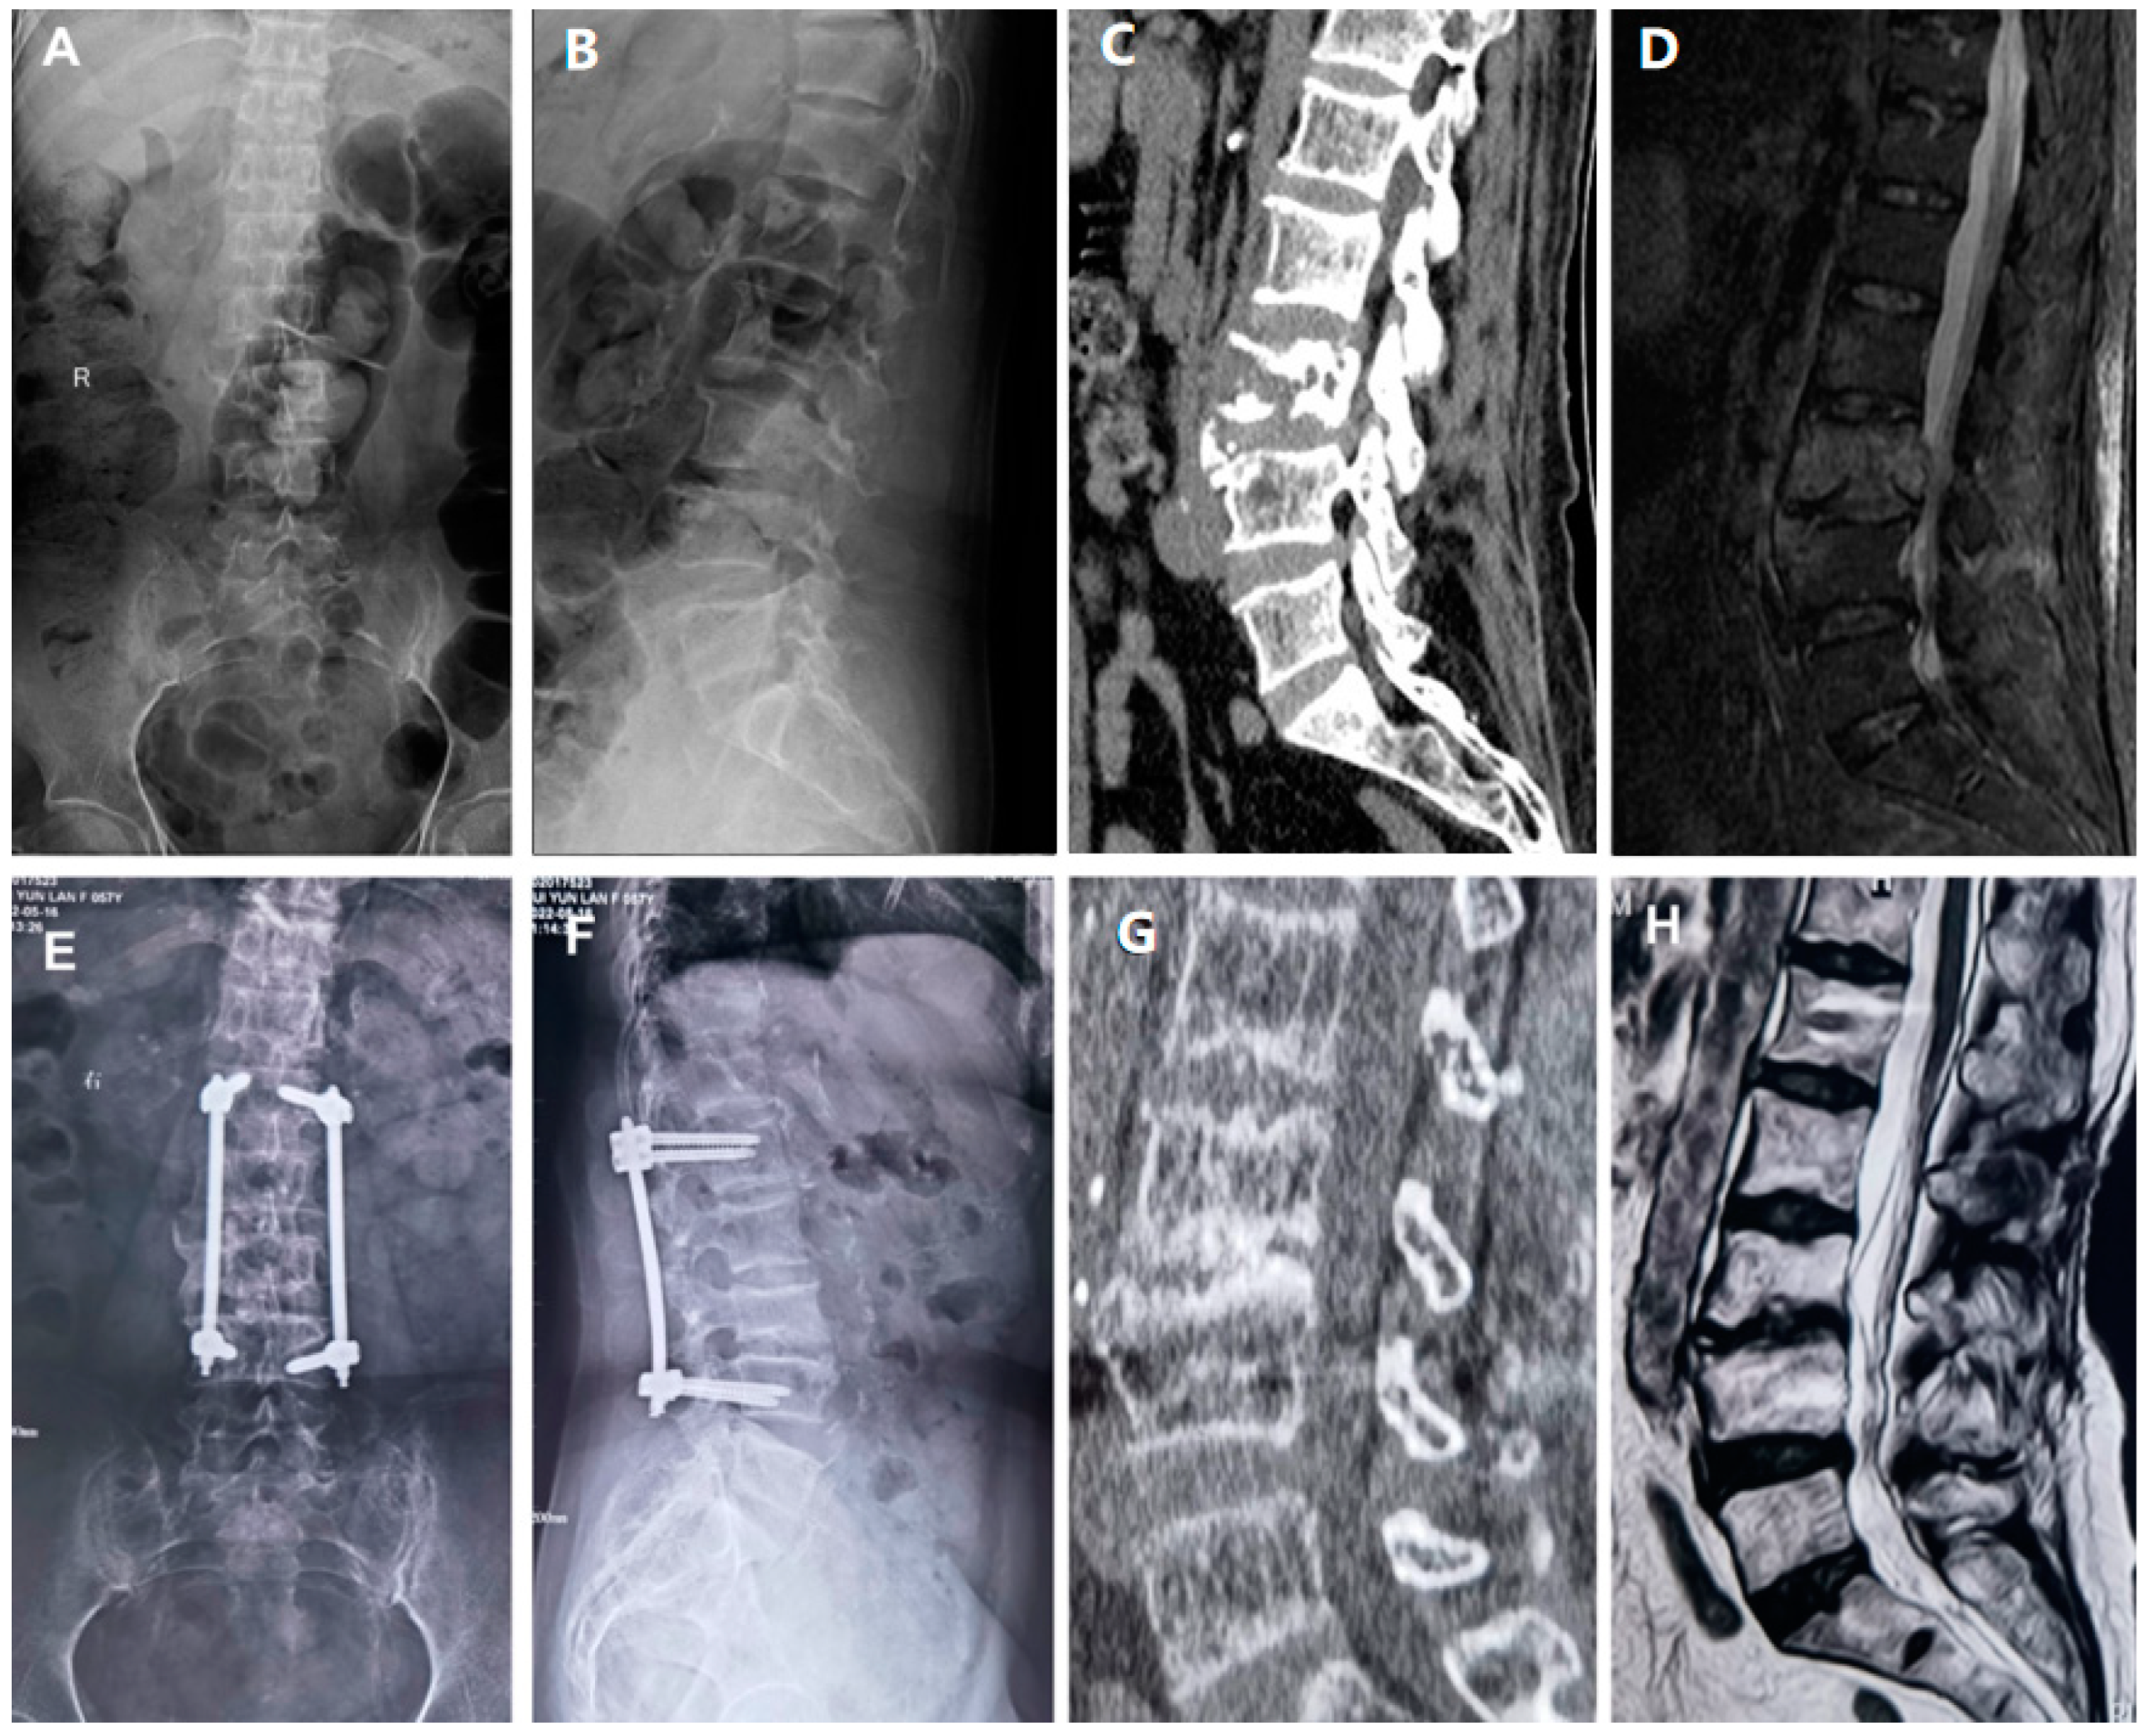

Figure 1.

Illustrative Case. A 54-year-old female patient was admitted to the hospital with a diagnosis of lumbar spine infection. Under general anesthesia, posterior debridement of lumbar spine lesions and percutaneous screw internal fixation with VSD suction was performed on 18 July 2019. On 25 July 2019, further lumbar spine lesion removal (L2/3) and VSD negative-pressure drainage were conducted. On 1 August 2019, lumbar spine lesion removal, lumbar intervertebral space bone grafting, and VSD negative-pressure drainage were conducted. (A,B) An admission X-ray showing the destruction of the vertebral bone. (C) Destruction of the L3 vertebral body seen on the admission CT. (D) Magnetic resonance imaging on admission showing signs of infection in the L3/4 intervertebral space. (E,F) X-rays 1 year after surgery showing an L3/4 fusion. (G) Fusion of the vertebral body seen on CT a year after surgery. (H) MRI showing the disappearance of signs of infection one year after surgery.